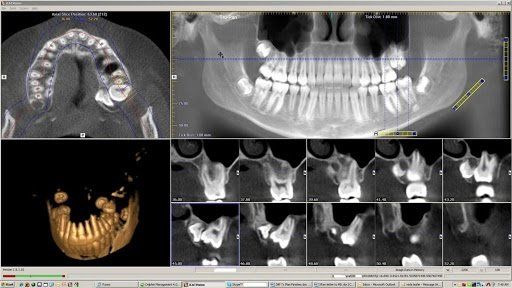

Ulteriore metodica di ultima generazione, la Cone Beam 3D, disponibile presso il Centro di Sciacca e di Ribera, si avvale di raggi X per acquisire una porzione del massiccio facciale, in particolare le arcate dentarie. La Cone Beam 3D viene utilizzata prevalentemente nella valutazione pre-operatoria in implantologia dentale.

Il macchinario di recente installazione che utilizziamo al Centro Radiologia Tagliavia, la Cone Beam Orthophos SL, permette l’acquisizione del volume desiderato in pochi secondi e attraverso le tecniche di post-processing e le ricostruzioni 3D, consente una migliore pianificazione pre-operatoria (misurazioni, densità) e una immediata visualizzazione delle arcate dentarie.

La Cone Beam 3D consente una riduzione nella dose di radiazioni somministrate rispetto a una TAC dentale, con buona qualità diagnostica limitatamente allo studio delle arcate dentarie: morfologia, altezza e spessore dell’osso sede di impianto, inclusioni dentarie (rapporti con il canale mandibolare), studio dell'articolazione temporo-mandibolare.